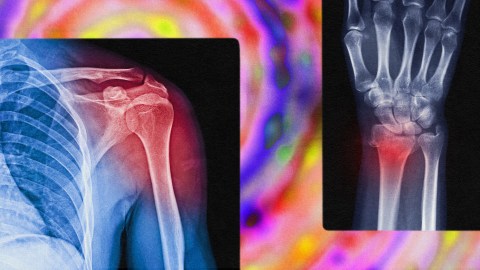

- Researchers are exploring how psychedelics might help the brain “snap out” of chronic pain, a condition that’s sometimes disconnected from any physical injury.

What if symptoms of chronic pain were sometimes just echoes of a past injury, and your brain could “snap out of it” with the help of psychedelics? It’s a surprising theory that several labs around the world are beginning to investigate. While there have been few double-blind, placebo-controlled, randomized clinical trials evaluating the efficacy of psychedelics for treating chronic pain, preliminary evidence is beginning to emerge — with promising results.